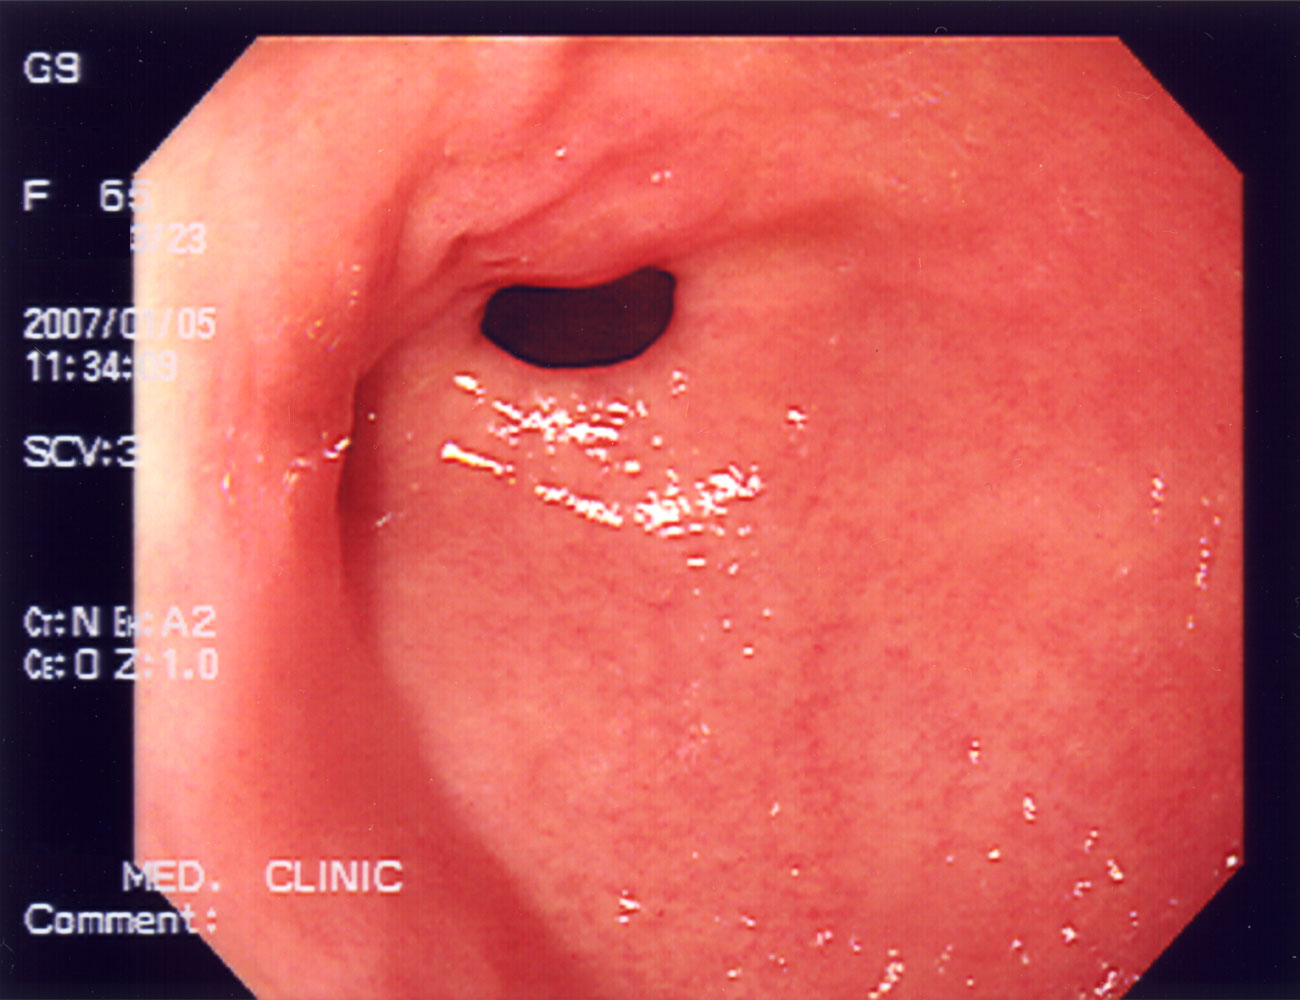

위선 폴립(polyp (medicine))의 내시경 사진